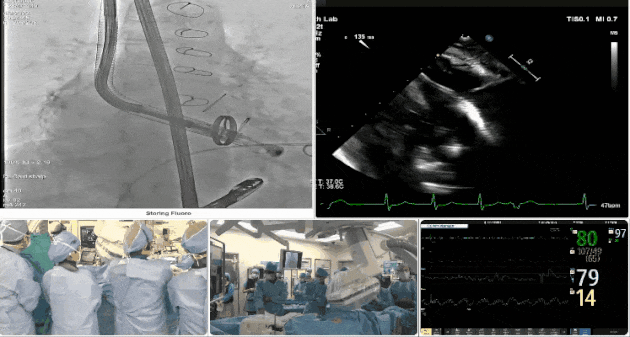

第三例患者手術(shù)難點(diǎn)

1、心率慢(<50bpm),術(shù)后起搏器植入風(fēng)險,術(shù)前需評估心電圖情況;2、CT顯示主動脈瓣機(jī)械瓣置換術(shù)后,需明確三尖瓣是否同期做過修復(fù)。

術(shù)中TEE觀察夾持件的位置

術(shù)后DSA

術(shù)后超聲評估瓣膜穩(wěn)定性良好,無瓣周漏

手術(shù)過程

術(shù)者采用經(jīng)右側(cè)頸靜脈入路的方式將輸送器送入患者心臟內(nèi),在TEE及DSA引導(dǎo)下調(diào)整輸送器頭端角度,使得輸送器與三尖瓣瓣環(huán)平面垂直。在輸送器進(jìn)入右心室后釋放室間隔錨定裝置,而后釋放瓣葉夾持件(2個耳片結(jié)構(gòu))成垂直狀態(tài)。在TEE及DSA確定夾持件固定至三尖瓣葉根部且位于右室側(cè)后釋放人工瓣心房側(cè)盤片。隨后調(diào)整瓣膜同軸性以及室間隔錨定件位置(貼合室間隔),前推藏針管并固定,進(jìn)而釋放室間隔錨定裝置,并再次確認(rèn)瓣膜位置、穩(wěn)定性及同軸性,合攏輸送鞘后撤出輸送器,最終順利完成LuX-Valve Plus人工三尖瓣瓣膜的植入。